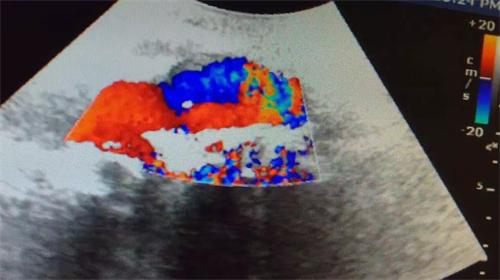

大腿軟組織腫脹處探查如圖所示,股淺動(dòng)脈管壁連續(xù)性中斷,可見撕裂口有血流噴 射。且該病灶探及動(dòng)脈頻譜,超聲提示:外傷后假性動(dòng)脈瘤形成